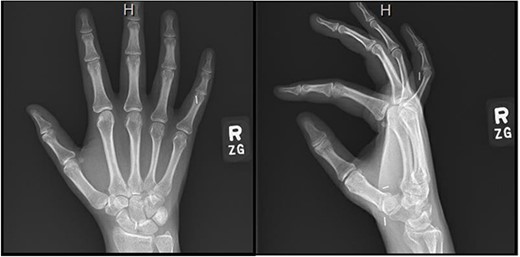

Repeat electromyography (EMG) and monofilament testing demonstrated some continued compression at the carpal tunnel and attempted nonoperative management included night splinting, physical therapy, and a corticosteroid injection (Fig. 1). The patient continued to vocalize complaints of right thumb numbness, sharp pain in her index finger, and an inability to distinguish temperature; therefore, she was subsequently scheduled for a revision CTR.

Semmes Weinstein testing values after redevelopment of right-hand symptoms [17].